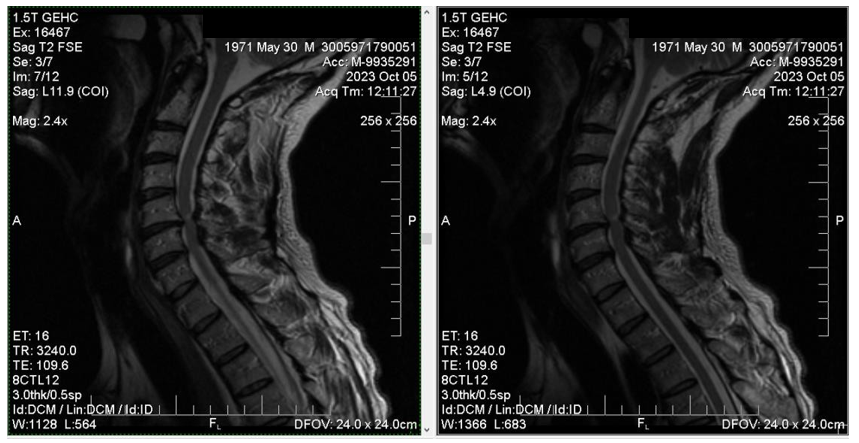

After returning to Uzice (patient’s hometown) from Belgrade, the treatment continues in a quantum medicine private clinic, where the BICOM bioresonance therapy was applied a number of times. After these therapies, the patient underwent rehabilitation treatment. The control MRI of the cervical spine was surprisingly better, as the edema was detected in only one point/area (Figure 3a & 3b), the clinical findings were considerably improved, the hyperesthesia reflexes were not as intense, the spasticity (i.e. the increased muscle tone) was lower than before, and the clonus, which was very pronounced, was hardly noticeable. Due to these results being significantly better than the findings of the first MRI scan, the surgical procedure was decided to be postponed until further notice.

Figure 3b The control MRI of the cervical spine